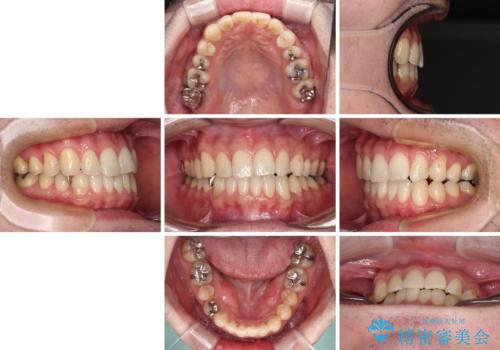

欠損のある歯列 インビザラインで整った歯並びに

- デコボコした前歯をセラミックできれいに揃えたいとのことで来院された患者様です。

歯を削って整えることは簡単ですが、健全な歯を削って後悔してからでは遅いため、矯正治療を提案しました。

はじめは矯正治療の期間が長いことに悩んでいらっしゃいましたが、ある程度整えば満足するだろうとのことで、インビザラインにて矯正治療を行うこととしました。

左上の犬歯が欠損しているため、正中の位置や奥歯の咬み合わせが理想的にならない点を了承していただきました。

インビザライン矯正は、1日22時間を目安に装着する必要がありますが、しっかりと装着してくださったので、順調に治療を進めることができました。